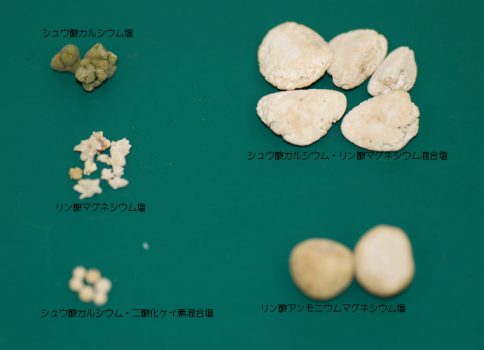

小さな膀胱結石による尿道尿道閉塞により緊急摘出手術した犬 シュウ酸カルシウム 青葉区の動物病院 院長堀川によるレオどうぶつ病院診療日記

膀胱結石 犬のシュウ酸カルシウム結石 – <お知らせ>.

8 犬の餌情報局 0528 フォローしました 人間にとっても、結石は激痛を伴う嫌な病気です。 犬の場合は、無症状で過ごしているケースもありますが、油断は禁物。 今回は、犬の結石の原因について勉強していくことにしましょう。 原因を知れば、飼い主さんとしてできる対策もできるので、愛犬をしっかりサポートしてあげてくださいね。 また 今は尿路. なぜ愛犬の膀胱炎は繰り返す?5つの原因 繰り返す原因1.膀胱に石ができている 膀胱に石ができることを膀胱結石といいます。 犬の膀胱結石の原因のほとんどは ・ストラバイト(リン酸アンモニウムマグネシウム) ・シュウ酸カルシウム のどちらかです。. わんちゃんの膀胱結石を手術治療しました 結石の種類や大きさなどにより治療方針が異なります 尿路結石は、おしっこの中に含まれるミネラルが何らかの原因によって塊となり、排泄されなくなってしまうことで起こります 膀胱でできた塊を膀胱結石といい、尿道でできた塊のことを尿道結石といいます 結石の種類はいくつかあります 1.リン酸アンモニウム.